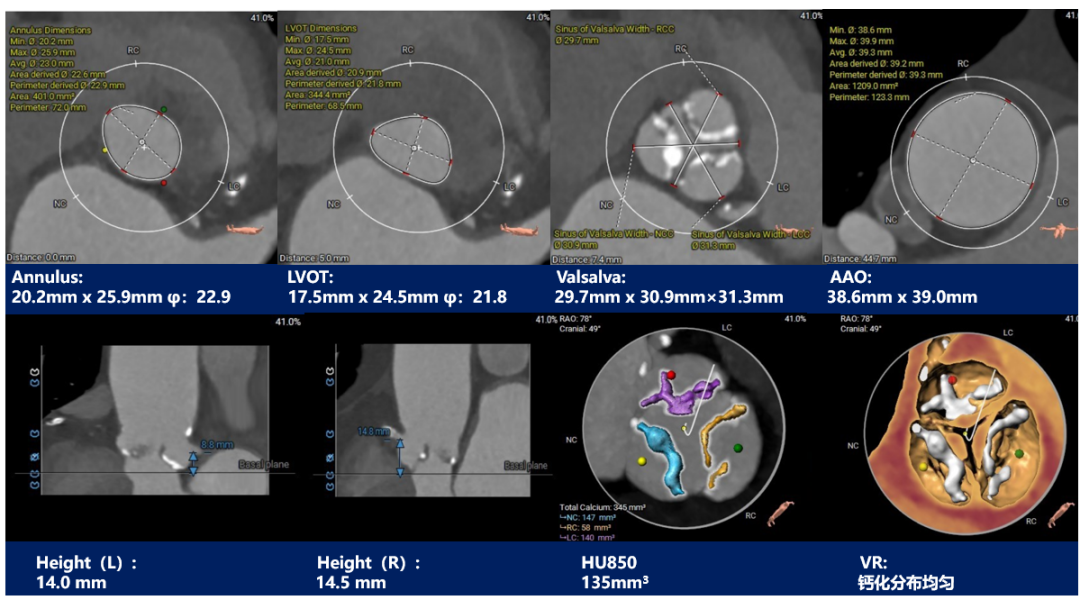

主动脉根部测量:

三叶式主动脉瓣,窦部发育均匀,瓣叶中重度钙化并纤维增厚,钙化分布相对均匀,主要分布在瓣叶边缘及管壁附着缘 ,右冠开口高度可,左冠开口高度偏低为8.8mm,左右冠脉切线位瓣叶长度>冠脉开口到瓣叶根部附着缘距离;冠脉可见钙化斑块。

主动脉根部评估:

三叶式主动脉瓣,中度钙化并瓣叶增生肥厚,钙化分布欠均匀,主要分布在瓣叶边缘及血管壁附着缘-左右冠高度可,冠脉切线位瓣叶长度<冠脉开口到瓣叶根部附着缘距离;冠脉可见散在钙化-流入端呈收口,瓦氏窦、STJ及升主动脉内径偏小。